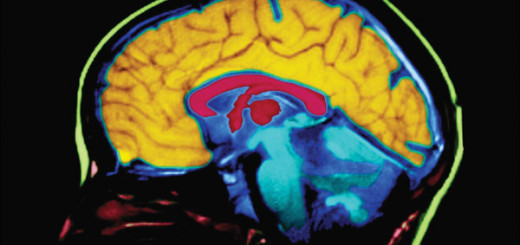

Sleep and the relationship to amyloid build-up

Scientists have conducted many studies examining the link between sleep and amyloid protein, which is a hallmark sign of Alzheimer’s. They found that shorter sleep duration and poor sleep quality are associated with greater amyloid build-up. But an association like this is not clear-cut evidence, since it is difficult to determine whether poor sleep causes greater amyloid deposits, or if it’s the other way around.

The research shows that build-up of amyloid in the brain is due to overproduction of amyloid, inability to get rid of excess amyloid, or both. It’s also been shown that amyloid concentration dips during sleep and peaks during awake hours. The more the scientists look at this relationship, the more indicators they have that poor sleep might be the cause of the amyloid build-up, and therefore an important risk factor for developing Alzheimer’s.